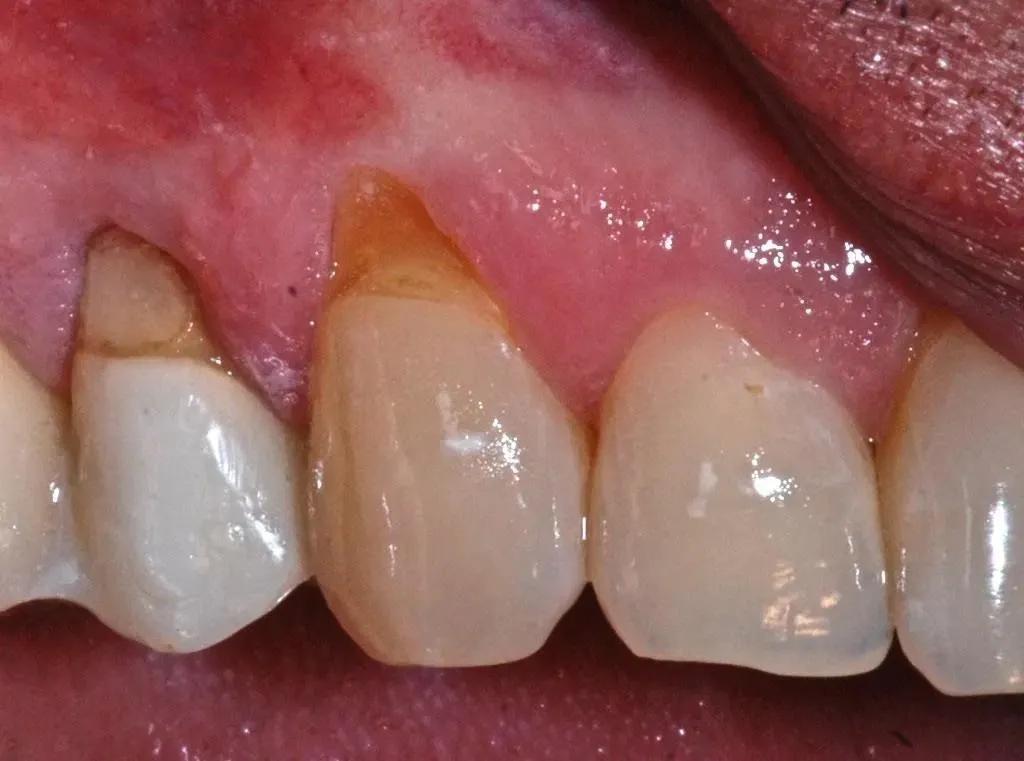

牙龈线后移,就是牙龈萎缩,简单地说,就是牙龈缘向根尖方向逐渐退缩,像海水退潮一样,暴露出牙根、牙缝,一笑起来,丑得很。

1、牙周炎

牙周炎是造成牙龈萎缩最常见的原因,而且这是一个无法逆转的过程,也就是说,一旦因为牙周炎发生牙龈萎缩,就不可能会好,甚至有时候,牙龈萎缩的“丑状”会在牙周炎治疗后更加明显,更加惨不忍睹。